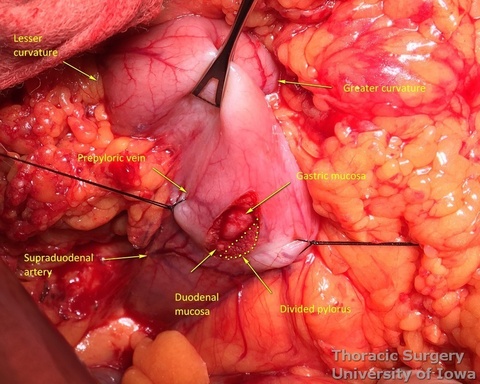

- Procced with mobilization of the stomach. The course of the right gastroepiploic artery is determined.

- The gastrocolic ligament is incised in its avascular portion between the terminal branches of the right and left gastroepiploic vessels, and the lesser sac is entered.

- The gastrosplenic ligament is divided towards the hiatus, taking care to stay away from the gastroepiploic arcade.

- Divide short gastric vessels with an energy device with care to avoid traction injury of the spleen.

- Fundus of the stomach is dissected free all the way to the esophageal hiatus dividing gastro-phenic ligament and remaining adhesions.

- The greater curvature of the stomach is then mobilized towards the pylorus, dividing the gastrocolic ligament no closer to than 1.5–2 cm to the right gastroepiploic vessels, while protecting the vessels with the fingers of the retracting hand. In morbidly obese patients the right gastroepiploic artery may not be visible or palpable. A Doppler probe is used then to identify its course and origin from the gastroduodenal artery.

- Posterior adhesions of the stomach are taken down.

- Peritoneum is incised, protecting the splenic artery and pancreas. 1-2 mm posterior gastric artery, originating from the proximal splenic artery fs present (in half of individuals) and is divided.

- Once the stomach is mobilized and reflected anteriorly, the left gastric vascular pedicle is identified and dissected close to the origin for adequate lymphadenectomy. Care is taken to not injure splenic artery and pancreas.

- Postradiation adhesions may be dense.

- Left gastric vessels are divided with an endoscopic linear cutting stapler proximally, including all adjacent lymph nodes in the specimen.

- Adequate mobility of the fully mobilized stomach is assured by the ability to bring the pylorus towards the hiatus.

- The Kocher maneuver is almost never needed.

- Injection of 200 units of Botox diluted in 8 mL of normal saline is performed anteriorly and posteriorly into the pylorus (divided in 2 mL portions in four quadrants) to improve gastric emptying postoperatively. No pyloromyotomy is needed then.

- Alternatively, pyloromyotomy can be performed using an electric cautery to divide the pyloric muscle.

- At approximately the level of the third large vein (accompanying vagal “crow’s foot”) along the lesser curvature, lymphatic tissue and vessels are mobilized and divided to expose the gastric wall.

- Starting from the lesser curvature of the stomach, several stapler loads are sequentially fired towards the fundus of the stomach, thus creating a 4–5 cm wide gastric conduit and ensuring a 5 cm margin distal to the tumor. Depending on the thickness of the stomach, medium purple or thick black (alternatively blue or green, depending on manufacturer) loads are used.